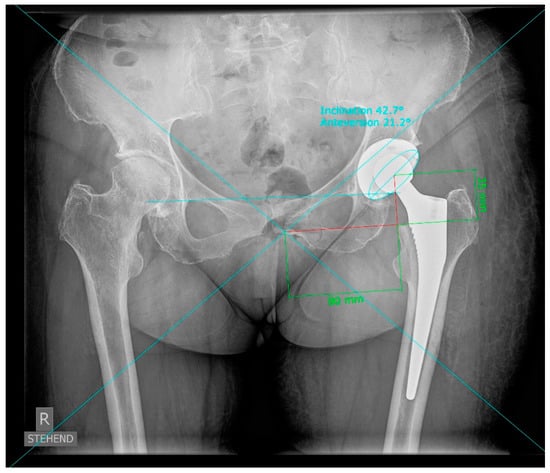

| X-ray Cup inclination APP radiographic (°) | 44.6 ± 5.3 |

| X-ray Cup anteversion APP radiographic (°) | 18.7 ± 6.0 |